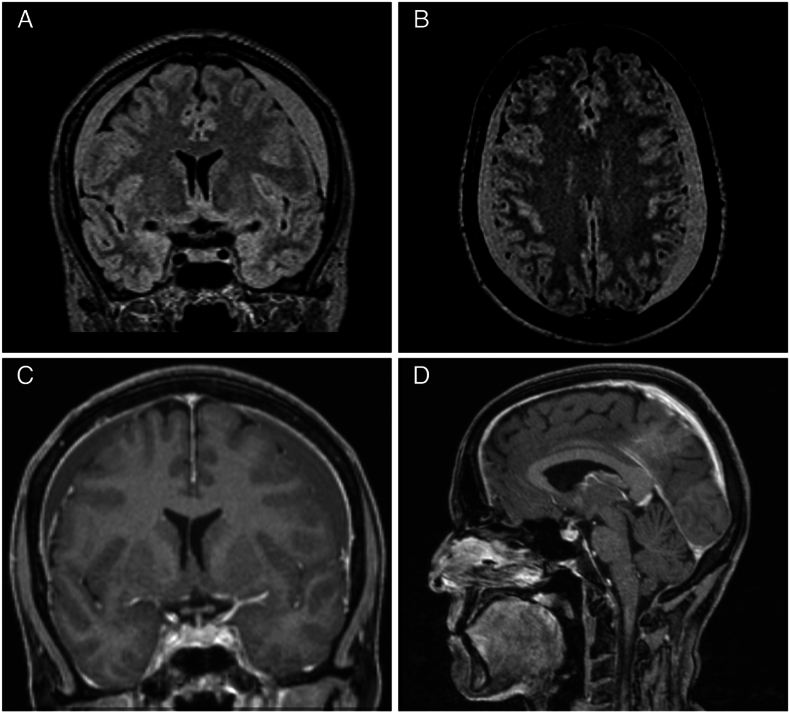

Results: Among 272 SIH patients, 85 (31 %) concomitantly had cSDH, predominantly bilateral (88 %). Hematoma width ranged from 2 to 30 mm. cSDH prevalence was highest in CSF-venous fistulas (43 %), followed by ventral (31 %) and lateral leaks (22 %). Male sex (OR = 4; p < 0.001) and age >70 years (OR = 6; p = 0.008) were significant risk factors. Surgical evacuation was performed in 23 patients, with symptoms attributable to cSDH in 17/23 patients. The biggest cSDH without surgical treatment was 20 mm. No neurological deterioration occurred during diagnostics or treatment of CSF leaks. After leak closure, no cSDH, regardless of initial size or previous treatment, required additional treatment, and no recurrence occurred in the 3-month follow-up.

Discussion and conclusion: Primary localization and targeted treatment of the spinal leak is safe in asymptomatic patients and cSDH ≤10 mm ("leak first" strategy). Immediate evacuation of the cSDH is mandatory in symptomatic patients ("subdural first" strategy). We consider the CSF leak closure as a causal treatment for cSDH resulting in a markedly low, close to zero, recurrence rate. Prospective validation of these findings is needed.